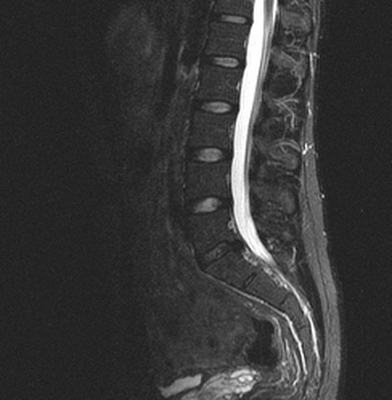

Множественные (2) гемангиомы на МРТ грудного отдела позвоночника